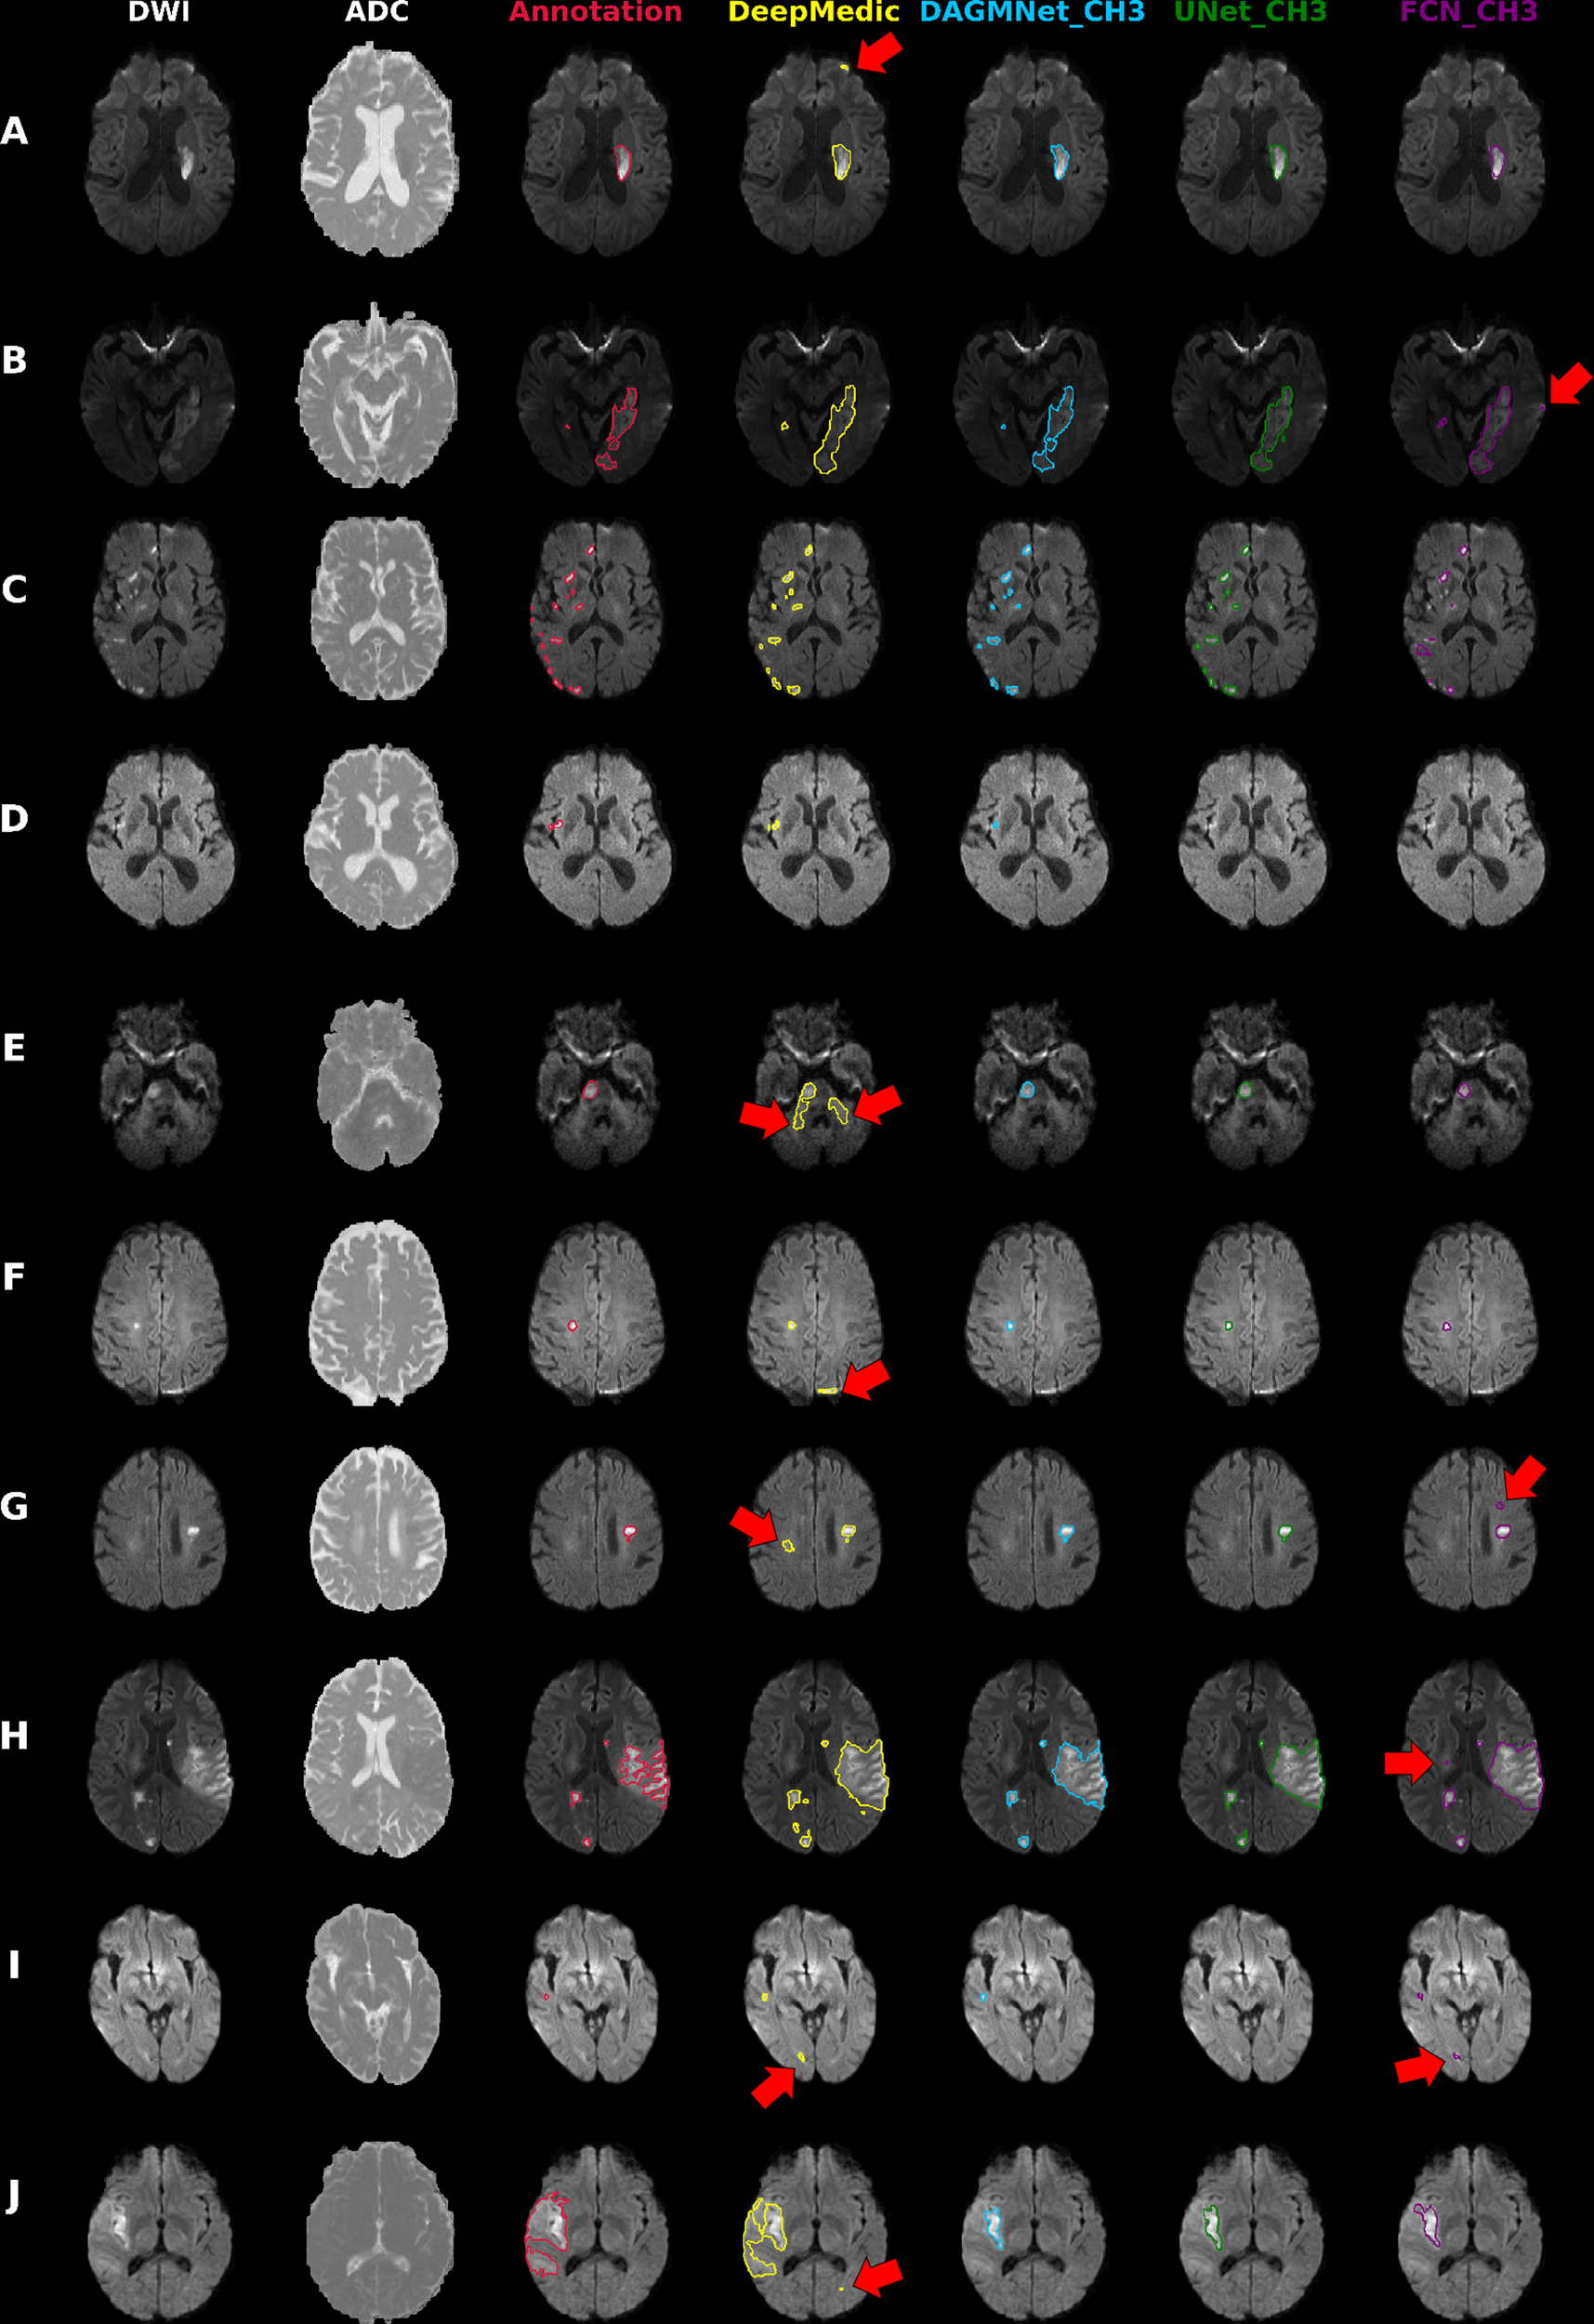

Fig. 7: Illustrative cases of models’ performances.

Columns from the left to the right: DWI, ADC, and overlays on DWI of the manual delineation (red), DeepMedic Predicts (yellow), DAGMNet_CH3 (our proposed model) predicts (blue), UNet_Ch3 (green), and FCN_CH3 (purple). A Typical lesion. B Case with inhomogeneity between DWI slices; note the high agreement of our proposed model with the manual annotation. C Multifocal lesions. D Small cortical lesion, detected exclusively by DeepMedic and our proposed attention model. E–G Typical false positives (arrows) of other models (DeepMedic in particular) in areas of: E “physiological" high DWI intensities; F DWI artifacts in tissue interfaces; in addition to the cortical areas, this was vastly observed in the basal brain, along the sinuses interfaces, and in the plexus choroids; G in possible chronic microvascular white matter lesions. H, I Cases in which the retrospective analysis favored the automated prediction, rather than the human evaluation for: H lesion delineation, and I lesion prediction (this case was initially categorized by evaluators as “not visible" lesion, but the small lesion predicted by our model was confirmed by follow-up). J Lesion of high-intense core but subtle boundary contrast, which ameliorates the discriminative power of all 3D networks. In this case, the patch-wise DeepMedic had the best agreement with manual annotation in the boundaries at the cost of detecting false positives (arrow).